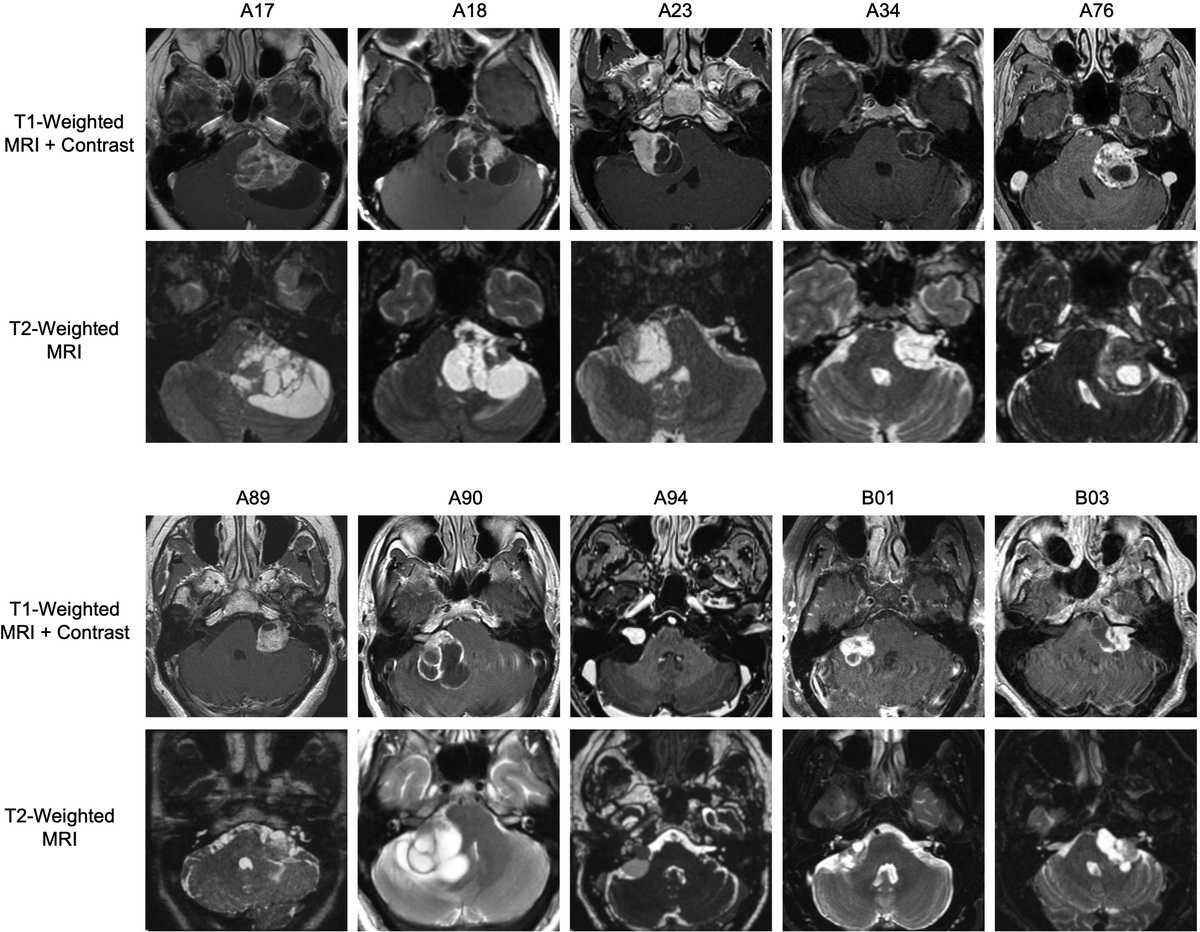

Metformin Reduces Tumor Growth in a Murine Flank Schwannoma Model

Hypothesis Metformin and aspirin reduce vestibular schwannoma (VS) growth. Background There